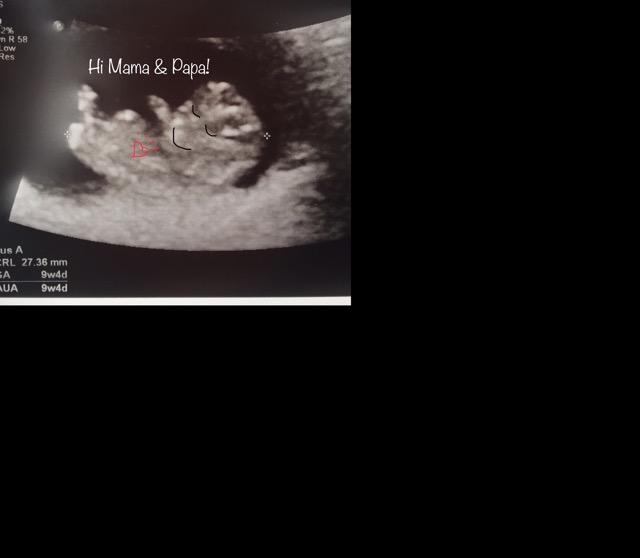

9+4 and the baby was kicking and waving! (Already looks like a little human but I added the features to send a picture to my husband since he couldn’t come to my scan today and he was bummed to miss it.)